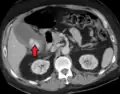

Right upper quadrant abdominal ultrasound is most commonly used to diagnose cholecystitis.[1][26][27] Ultrasound findings suggestive of acute cholecystitis include gallstones, pericholecystic fluid (fluid surrounding the gallbladder), gallbladder wall thickening (wall thickness over 3 mm),[28] dilation of the bile duct, and sonographic Murphy's sign.[13] Given its higher sensitivity, hepatic iminodiacetic acid (HIDA) scan can be used if ultrasound is not diagnostic.[13][14] CT scan may also be used if complications such as perforation or gangrene are suspected.[14]